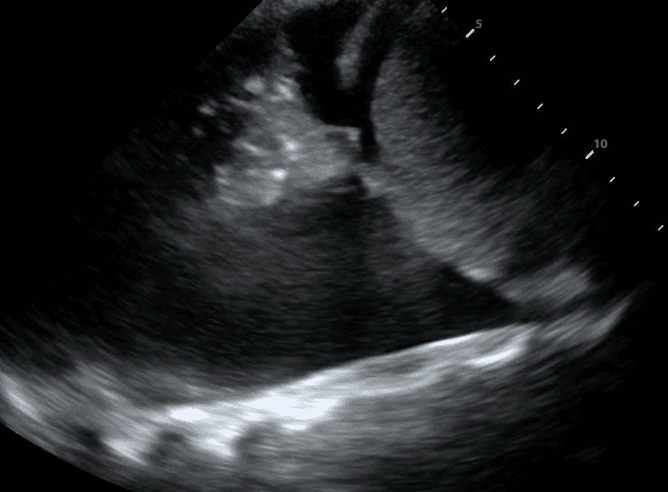

A sick patient arrives in the ICU and a central line was recently placed. Suddenly, the patient’s oxygen levels drop and they develop hypotension. The nurse is worried about pneumothorax - a life-threatening diagnosis where the lung collapses. The patient is too sick at this point to go down for an x-ray and there is only one portable x-ray technologist available in the hospital at this time of night.

However, with bedside ultrasound, the nurse could accurately rule out pneumothorax and assess for other dangerous conditions of the lung.

It’s 2 am in a busy thoracic surgery unit when the call bell goes off. When the bedside nurse comes to the room, they find their patient is sitting at the side of the bed struggling to catch their breath. Their vital signs show that they have an abnormal heart rate and low oxygen levels. The doctor has gone home for the night and when called, orders a chest x-ray to rule out pleural effusion - a dangerous accumulation of fluid in the chest cavity that may require immediate drainage.

Unfortunately, the portable x-ray technologist is busy with another patient. With bedside lung ultrasound, the nurse could rapidly identify pleural effusion with high accuracy and facilitate treatment.